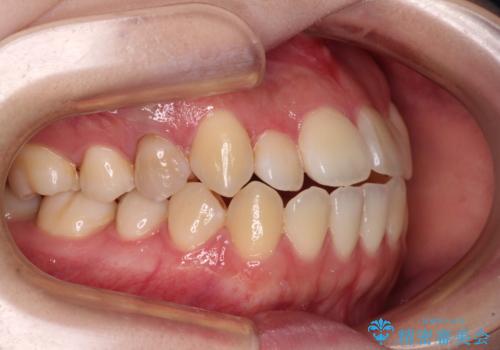

舌突出癖による開咬 舌のトレーニングを行いながら前歯の隙間を改善

- 上下前歯の隙間を気にして来院された患者様です。

前歯が、舌の突出癖により上下前歯が非接触となっている状態でした。

上下前歯が非接触である開咬は、インビザラインによる治療がお勧めではありますが、しっかりと使う自信がないとのことで、ワイヤー装置にて治療を行うこととしました。